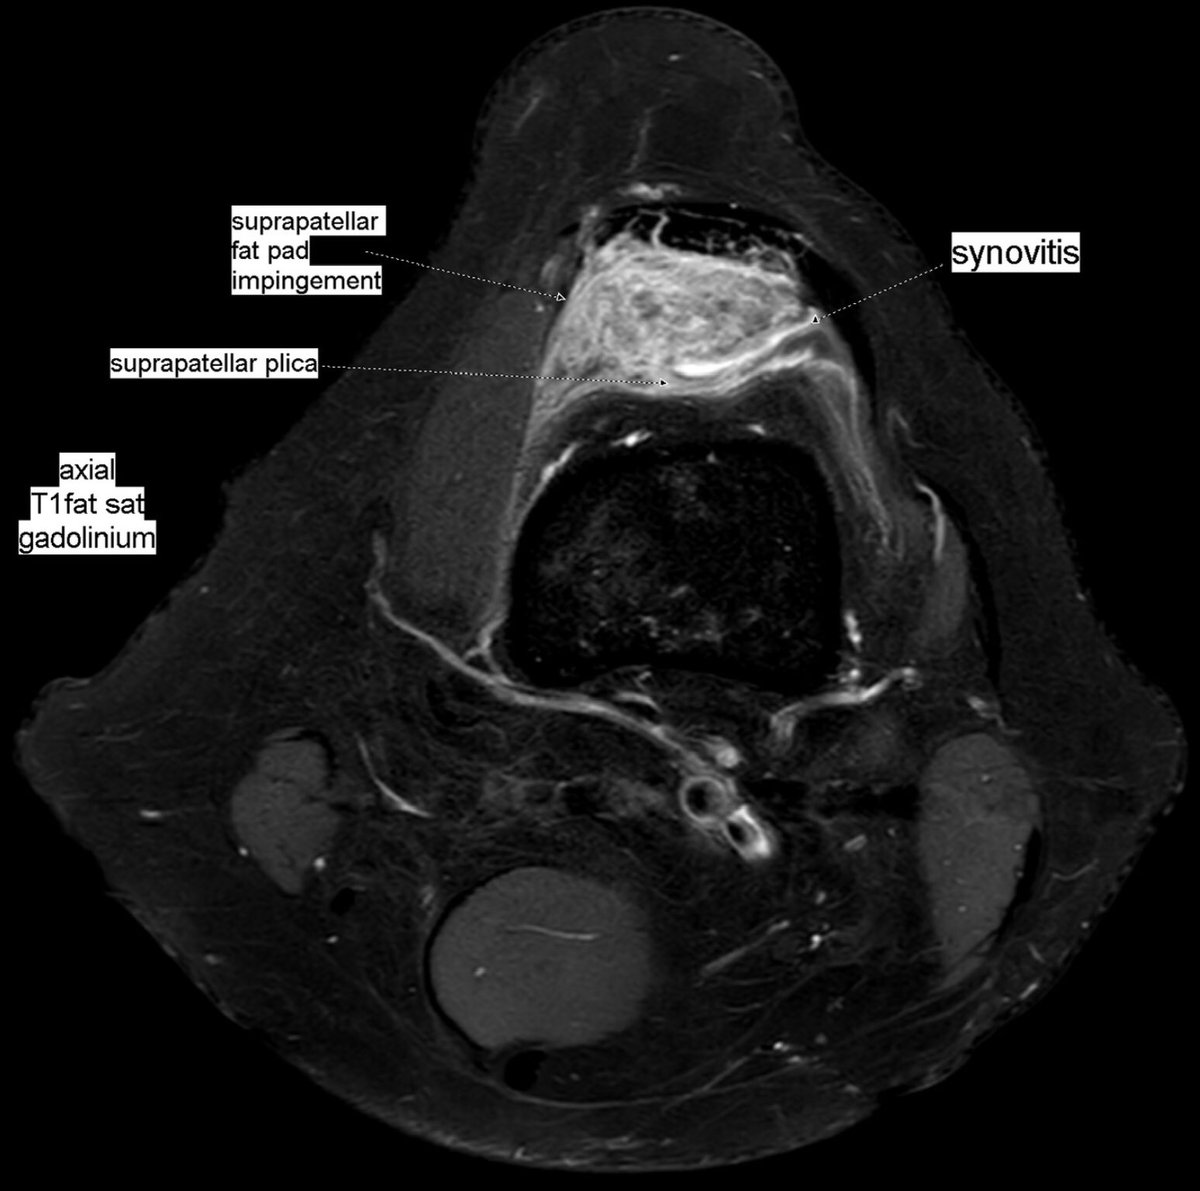

Patient with anterior knee pain. Localized synovitis of suprapatellar recess and suprapatellar fat pad impingement syndrome secondary to a suprapatellar plica: suprapatellar plica syndrome.

#MSKrad#knee#orthopaedics#radiology https://www.ncbi.nlm.nih.gov/pmc/articles/PMC6477514/pdf/main.pdf …pic.twitter.com/fvk7MUuDNt